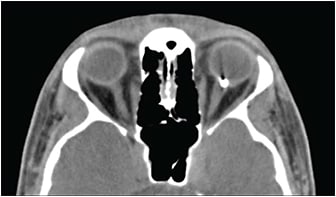

Imaging

Imaging is a very important part of the workup of a patient with an OGI. Computed tomography (CT) scans are fast, widely available, and effective at detecting a wide range of foreign bodies.6 Thin (1-mm) cuts with coronal (Figure 5), axial (Figure 6), and sagittal views are ideal to identify IOFBs and to assess the globe contour, site of posterior rupture, and any other cranial (eg, subarachnoid hemorrhage) or ophthalmic traumatic sequelae (eg, orbital fractures or retrobulbar hemorrhage). Although CT is able to detect most IOFBs well, wood IOFBs are usually hypodense and may be mistaken for air or fat.7 The presence of linear-appearing air should raise suspicion for a wood IOFB. Measuring the Hounsfield units of an IOFB identified on CT may provide some insight into its composition.6